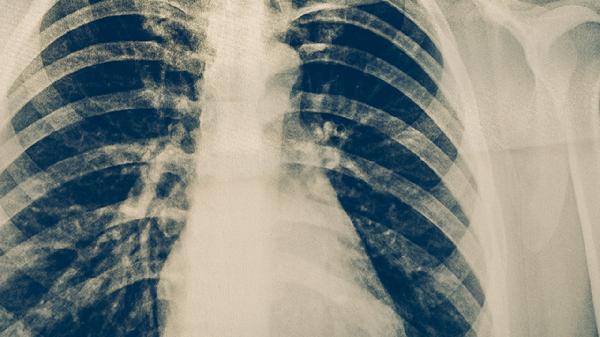

與活動性肺結(jié)核患者共處一室時,雙方均應佩戴醫(yī)用防護口罩,保持1米以上距離?;颊呖人?、打噴嚏時需用紙巾遮掩口鼻,痰液應吐入含消毒液的專用容器。家庭成員中出現(xiàn)患者時,其他成員需進行結(jié)核菌素試驗和胸部X線篩查。

高危人群如醫(yī)務人員、矽肺患者、免疫功能低下者,建議每年進行胸部X光檢查。持續(xù)咳嗽咳痰超過2周、低熱盜汗消瘦者,應及時做痰涂片和結(jié)核菌素試驗。早期發(fā)現(xiàn)潛伏感染者可通過3-9個月的藥物預防,降低發(fā)病概率。